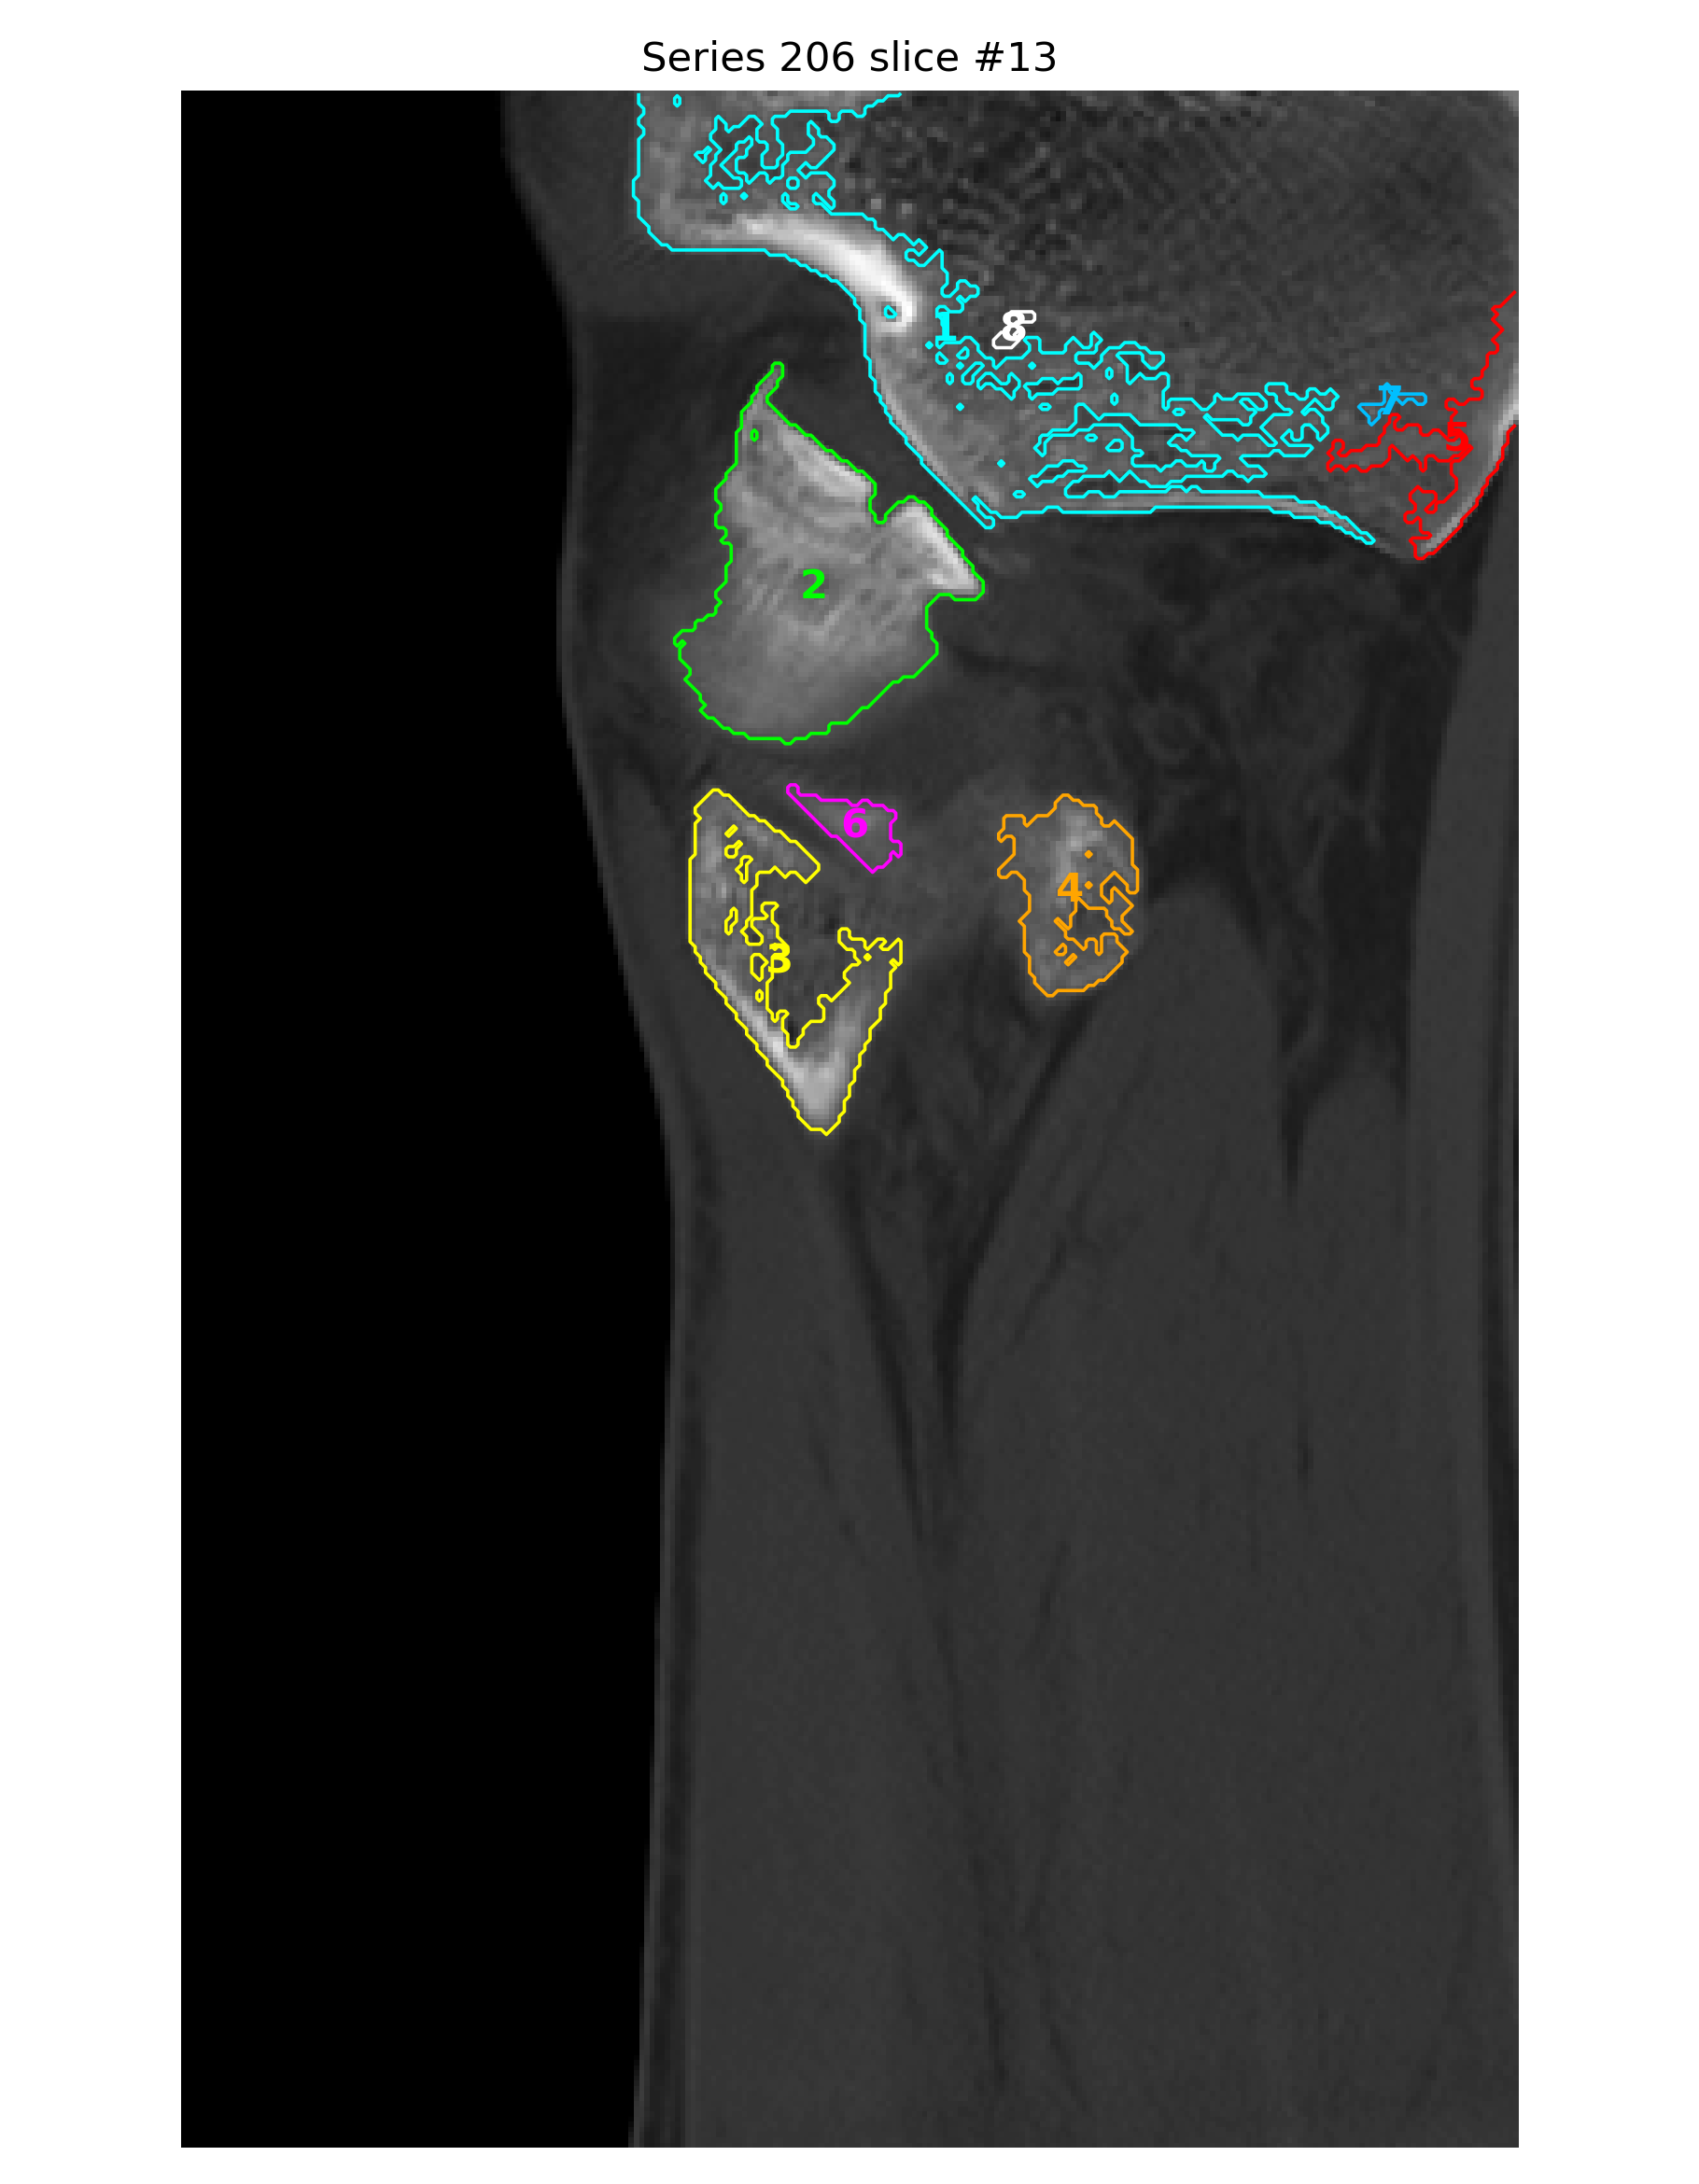

基于 2026-04-02 右踝无对比 CT 原始 DICOM 的辅助分析。核心问题是: 右踝外侧、距骨外侧突及距下关节外侧附近存在高概率关节内骨性损伤, 表现更接近单板滑雪常见的 snowboarder’s fracture。

- 异常位置集中在外踝前下方、距骨外侧突附近、距下关节外侧缘附近。

- 冠状位、矢状位和三维辅助重建里都能反复看到局部骨性不规则和分离感。

- 近似测量多次落在 2.0、2.3、2.8、3.3 mm 这个量级,支持轻度位移。

三维与关键切面

三维图更适合看骨片和关节面的空间关系;真正判断骨折线、关节面台阶和位移, 仍然要以原始 CT 切面为主。

定量分析与标注图

以下毫米值为近似测量值,作用是帮助沟通位移量级,不等同于医生在工作站上的正式卡尺读数。